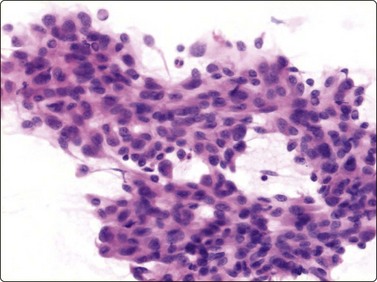

Merkel cell carcinoma (neuroendocrine carcinoma of skin) (Fig. 14.17, and see Fig. 5.23)61,62

image

Fig. 14.17 Merkel cell carcinoma

(A) Poorly cohesive cells; nuclear pleomorphism and some molding, scanty blue cytoplasm resembling lymphoid cells (MGG, HP); (B) Cellular smear of dispersed small cells with round, dark nuclei (Pap, HP); (C) Dot-like positive staining with CAM5.2 (immunostaining, HP).

Criteria for diagnosis

Cell-rich smears of mainly dispersed small neoplastic cells,

Fragile, scanty, blue (MGG) cytoplasm; high nuclear : cytoplasmic ratio; many stripped nuclei,

Clustered cells may show nuclear molding and rosette-like grouping,

Round or ovoid, mildly to moderately irregular hyperchromatic nuclei with inconspicuous nucleoli,

Mitoses frequent,

Lymphoid globules (lymphoglandular bodies) absent,

Dot-like paranuclear staining for cytokeratin; chromogranin usually positive.

Primary neuroendocrine carcinoma of skin is an uncommon neoplasm, mainly seen in elderly patients and most often in the head and neck. It is locally aggressive and often metastasizes to regional lymph nodes. Clinically and cytologically, Merkel cell tumor can be difficult to distinguish from non-Hodgkin lymphoma when it presents as lymphadenopathy without an obvious primary, as is often the case (see Chapter 5).

Page 379

Smears are usually highly cellular. The cells are mainly dispersed but some are clustered or form single files with nuclear molding and sometimes rosette-like groups. The main differential diagnoses are lymphoma and metastatic small cell carcinoma. Amelanotic melanoma may also be considered. The absence of lymphoid globules in the background and subtle differences in nuclear chromatin help in this distinction. Staining for CAM5.2, CK7 and CK20 demonstrates characteristic dot-like intracytoplasmic deposits in the tumor cells (Fig. 14.17C), and staining for neuroendocrine markers is usually positive. Electron microscopy shows well-demarcated whorls of cytoplasmic filaments.